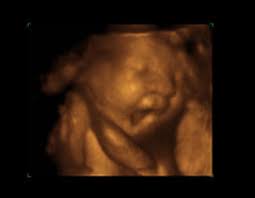

Artık ağırlığı bir kiloyu geçen bebeğiniz, vücudunuza yaptığı baskıyı

gitgide artıracaktır. Bu baskı da size, her geçen gün artan, ayak şişme ve

ağrıları, bel ağrıları, kasık ağrıları, basur, sık idrara çıkma, mide yanması,

hazımsızlık vb. şeklinde geri dönecektir.

Artık bebeğiniz de doğuma hazırlık için baş aşağı pozisyonunu

Bebeğinizin hareketleri azalmakla beraber daha fazla hissedilir

olacaktır. Uzun süre hareketsizlik hissederseniz mutlaka doktorunuza bildirin.